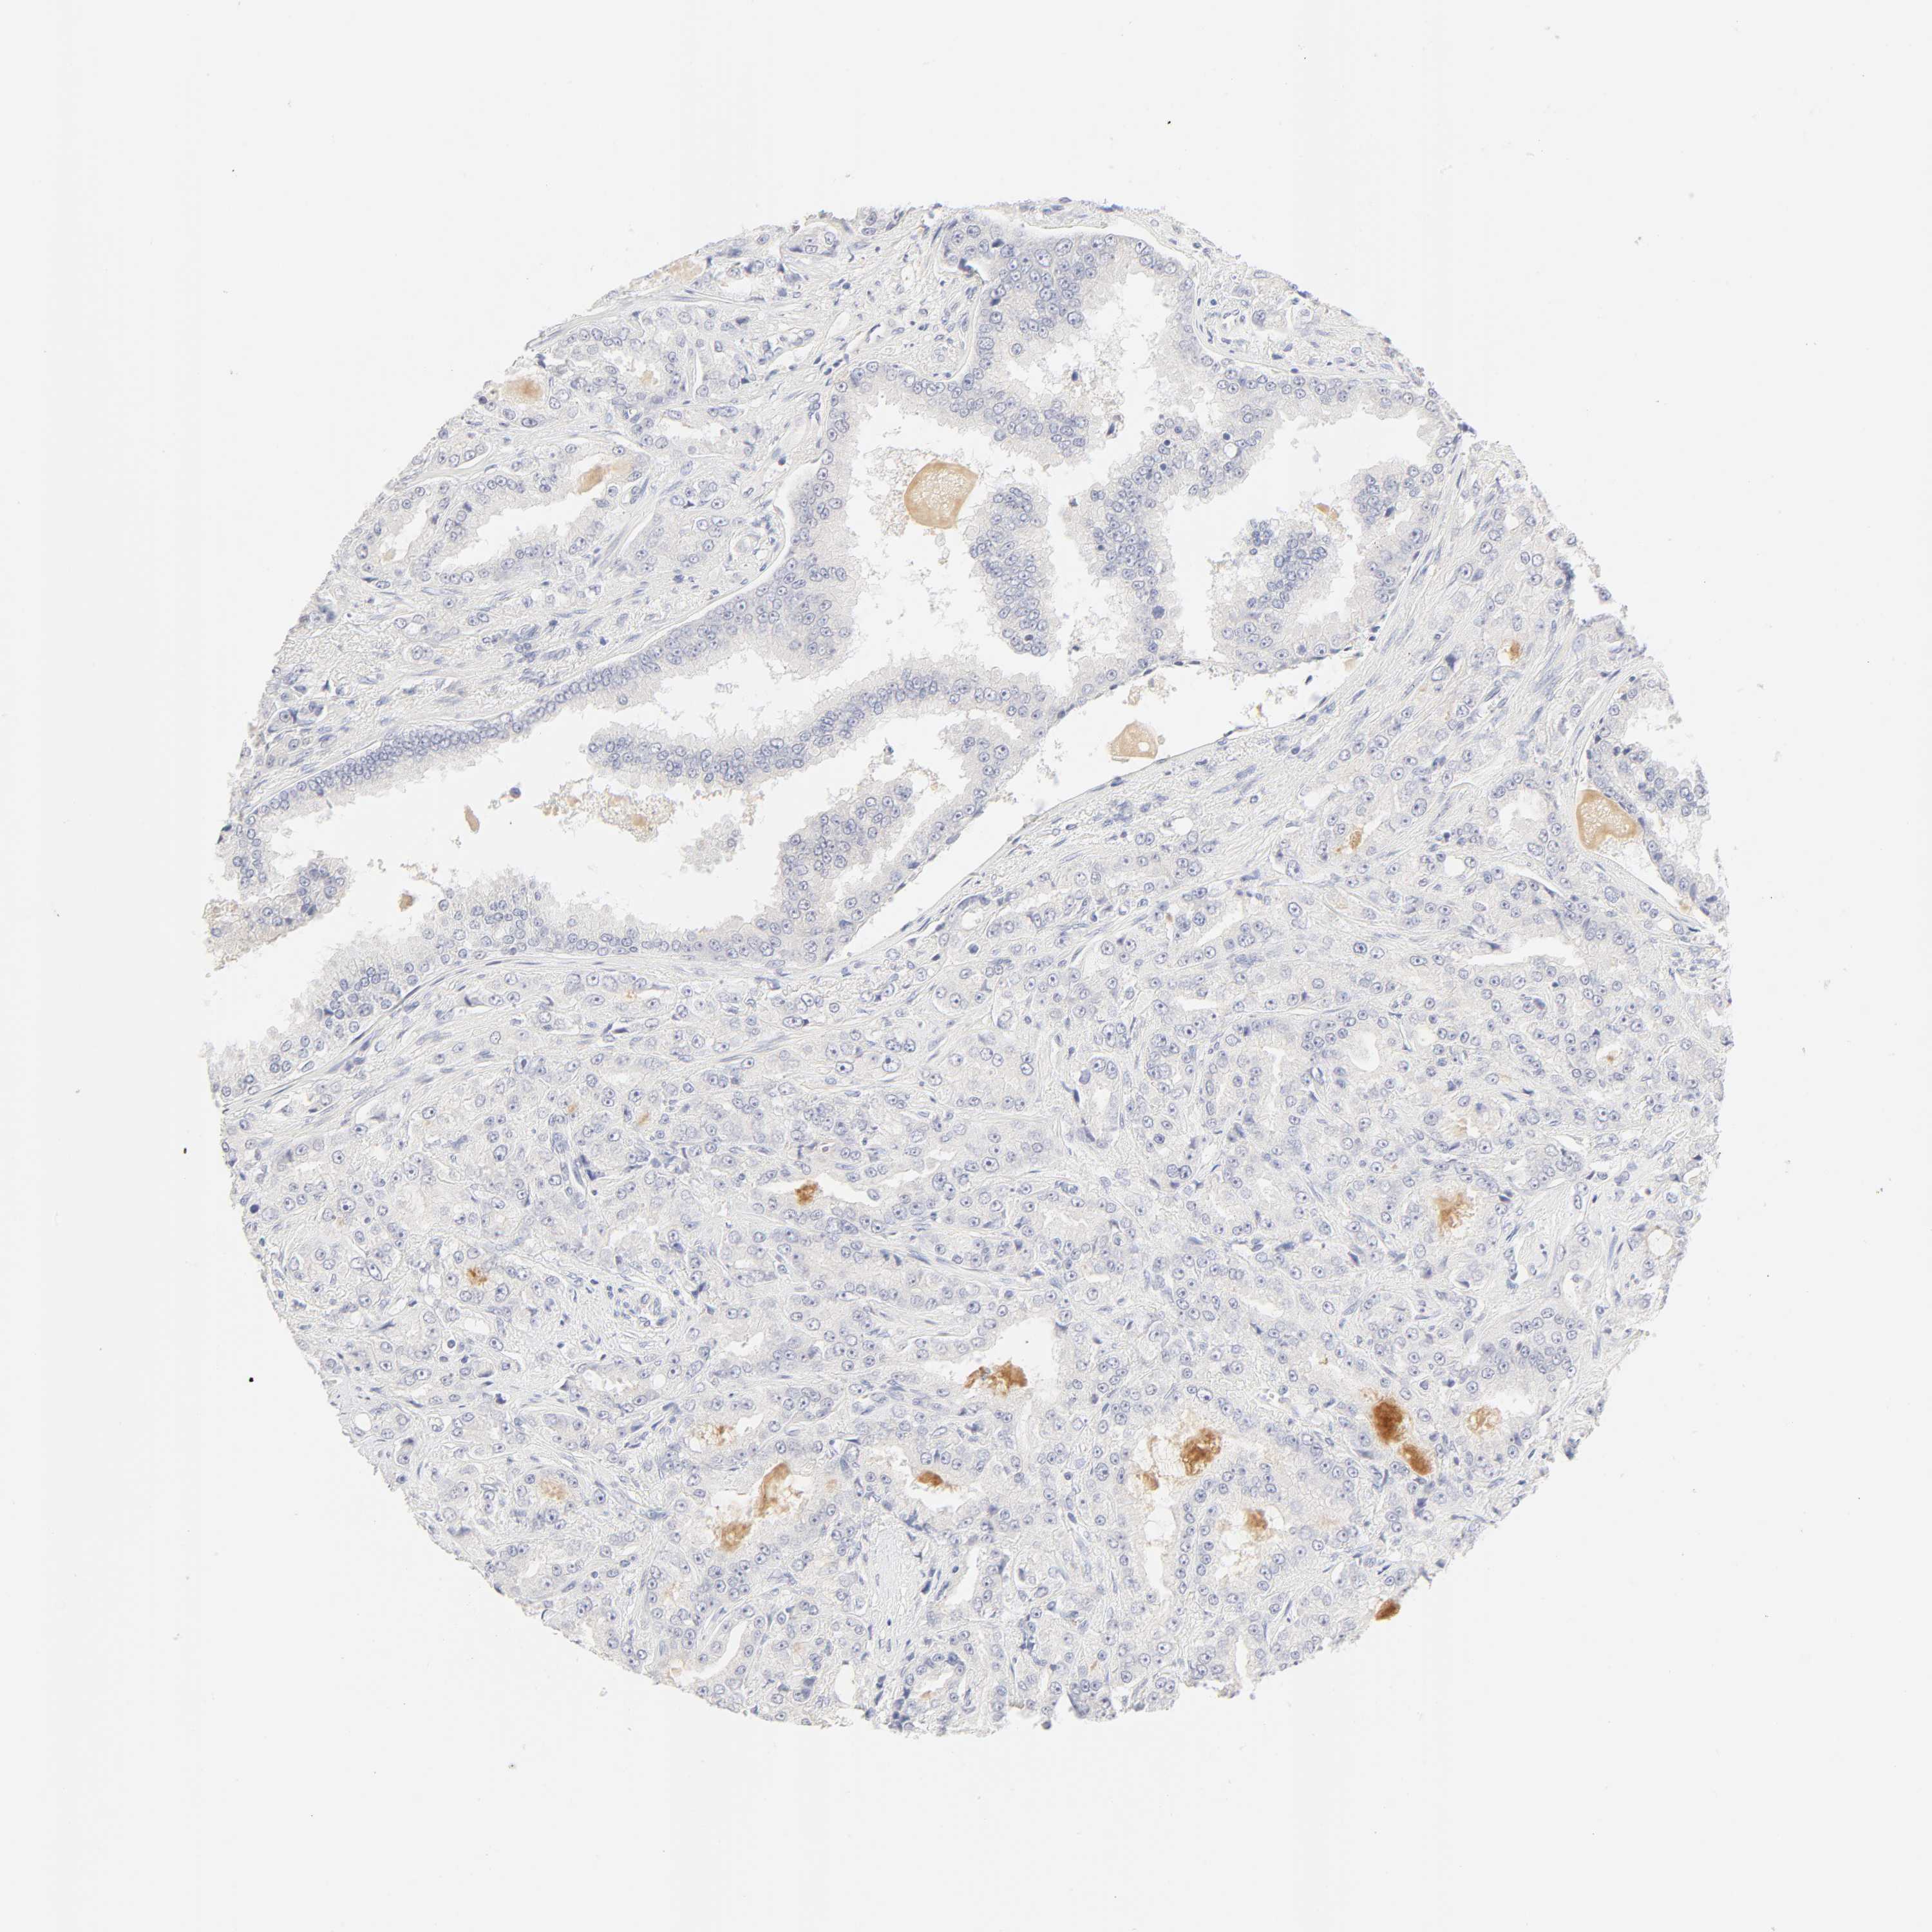

PROSTATE CANCER - Protein expressioni

A mouse-over function shows sample information and annotation data. Click on an image to view it in a full screen mode. Samples can be filtered based on level of antibody staining by selecting one or several of the following categories: high, medium, low and not detected. The assay and annotation is described here.

Note that samples used for immunohistochemistry by the Human Protein Atlas do not correspond to samples in the TCGA dataset.

Antibody stainingi

Antibody staining in the annotated cell types in the current human tissue is reported as not detected, low, medium, or high, based on conventional immunohistochemistry profiling in selected tissues. This score is based on the combination of the staining intensity and fraction of stained cells.

Each image is clickable and will lead to virtual microscopy that enables deeper exploration of all samples and also displays staining intensity scores, fraction scores and subcellular localization as well as patient and tissue information for each sample.

Antibody HPA004331

Staining

High

Medium

Low

Not detected

Intensity

Strong

Moderate

Weak

Negative

Quantity

>75%

75%-25%

<25%

None

Location

Nuclear

Cytoplasmic/membranous

Cytoplasmic/membranous,nuclear

Adenocarcinoma, Low grade

Adenocarcinoma, High grade